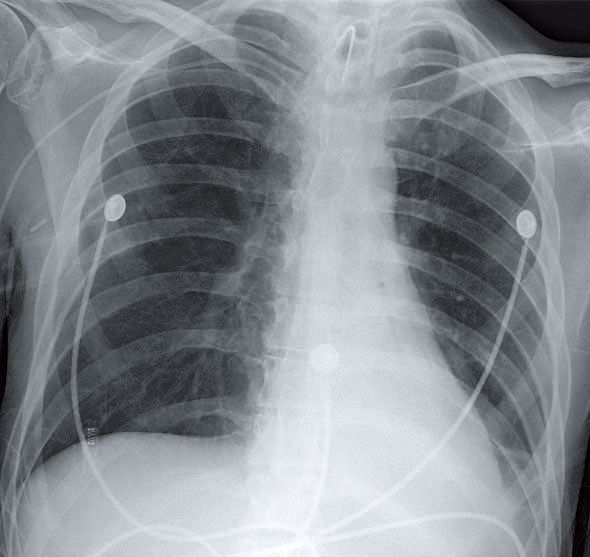

Patient with Myasthenia Gravis and Hypoxia Post category:Spot Diagnosis Post published:February 28, 2026 Share on Facebook Share on X (Twitter) Share on Pinterest Share on Email Share on Reddit CXR of a Patient with Myasthenia Gravis and Hypoxia 28-year-old man with a history of myasthenia gravis is noted to be hypoxic. What’s the diagnosis ? FULL CASE AND ANSWER Share on Facebook Share on X (Twitter) Share on Pinterest Share on Email Share on Reddit Read more articles Previous PostWoman with a History of a Mitochondrial Myopathy Next PostSwelling of the Hands You Might Also Like Hyperkeratosis, Papillomatous Plaques, and Loosely Adherent Crust on Legs December 15, 2021 Patient with Symptoms of Eye and Ear Pain March 31, 2022 Patient with Acute Dyspnea and Chest Pain and a History of Peptic Ulcer April 10, 2022